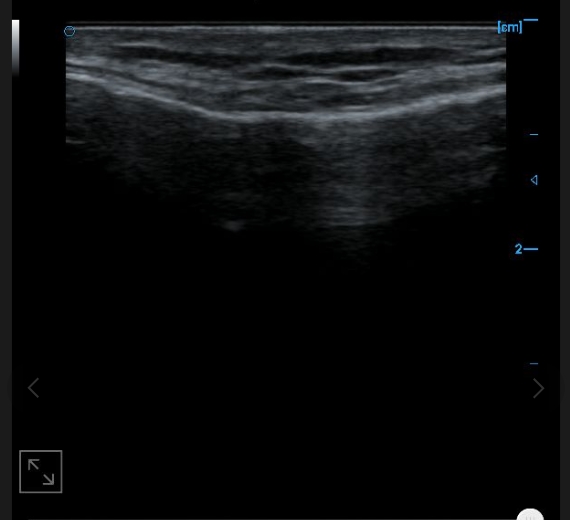

B-image of quadriceps tendon